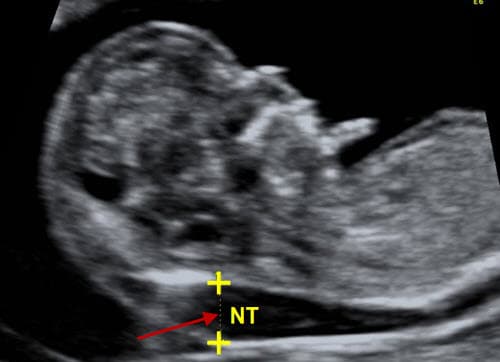

Khoảng sáng sau gáy là gì? xuất hiện từ tuần thứ 11 đến 13

Khoảng sáng sau gáy của thai nhi là độ mờ của vùng da sau gáy, xuất hiện từ tuần thứ 11 đến 13 của thai kỳ. Đo khoảng sáng sau gáy là một trong những phương pháp giúp xác định khả năng mắc hội chứng Down ở trẻ. Khoảng sáng sau gáy là gì? Khoảng […]

Độ mờ da gáy bao nhiêu là bình thường?

Độ mờ da gáy bao nhiêu là bình thường là điều được nhiều mẹ bầu quan tâm. Xét nghiệm đo độ mờ da gáy là chỉ định của bác sĩ mà mẹ bầu nào cũng nên thực hiện. Đo độ mờ da gáy là gì? Đo độ mờ da gáy là cách tiến hành siêu […]